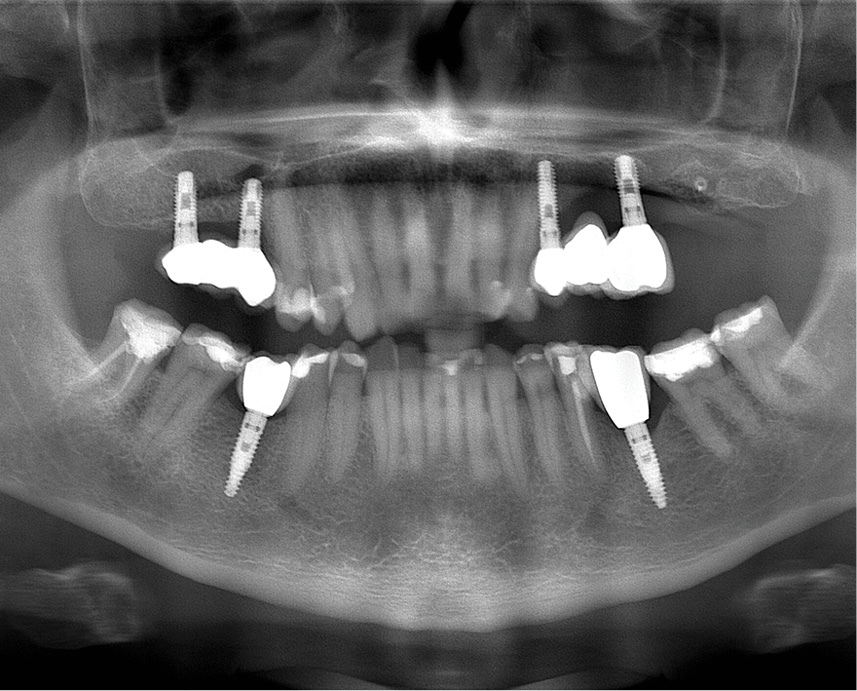

Streszczenie: Periimplantitis jest to stan zdefiniowany jako reakcja zapalna wokół zintegrowanych implantów prowadzący do postępującej utraty kości. Różne metody leczenia są sugerowane w leczeniu zapalenia okołowszczepowego. Na podstawie opisanego przypadku klinicznego pragniemy pokazać możliwości zastosowania lasera diodowego w leczeniu zapalenia wokół implantów.

Summary: Periimplantitis is a state defined as an inflammatory reaction around osseointegrated implants, leading to progressive loss of supporting bone. Various treatment methods are suggested in the treatment of peri-implantitis. Based on the clinical case described below, we want to show the possibilities of using a diode laser in the treatment of inflammation around implants.

W dzisiejszych czasach coraz częściej wykorzystywane implanty dentystyczne wydają się skutecznym sposobem leczenia częściowo lub całkowicie bezzębnych pacjentów. Jednakże nawet w obrębie zintegrowanego z kością wszczepu mogą pojawić się komplikacje. Periimplantitis jest to stan zapalny, który obejmuje swoim zasięgiem tkankę miękką oraz przyczynia [...]